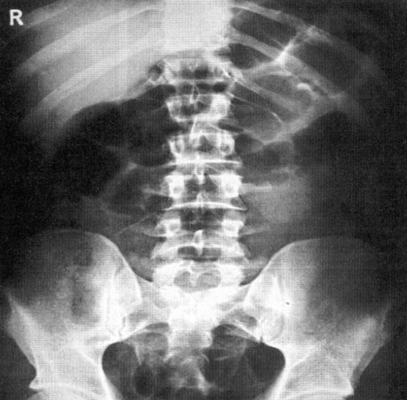

Рентгенография брюшной полости

Рентген активно используется для диагностики заболеваний органов брюшной полости. Широко распространена обзорная рентгенография брюшной полости - рентгенографическое исследование без введения контрастного вещества, позволяющая получить общую картину состояния брюшной полости.

Что показывает рентген брюшной полости?

Метод рентгендиагностики основан на том, что ткани различной плотности по-разному поглощают рентгеновские лучи. Более плотная, например, костная ткань хуже пропускает лучи, поэтому на снимке такая ткань оказывается светлее. Метод позволяет определить местоположение органов, их целостность, наличие инородных тел и новообразований.

Рентгенография брюшной полости показывает:

- как распределены газ и жидкость в брюшной полости, присутствует ли в брюшной полости свободная жидкость;

- присутствуют ли в брюшной полости инородные тела (проглоченные предметы в кишечнике, камни в желчном пузыре, камни в почках);

- имеются ли повреждения внутренних органов;

- имеет ли место внутрибрюшное кровотечение.

Рентген брюшной полости

С точки зрения оценки состояния конкретных органов обзорная рентгенография брюшной полости не очень информативна, однако она позволяет быстро определить, является ли картина патологической или нет. При разрыве стенки желудка или кишечника (прободение язвы или разрушении стенки опухолью) рентген покажет выходящий в свободную брюшную полость газ. С помощью рентгена брюшной полости можно диагностировать непроходимость кишечника и даже определить примерное место локализации проблемы.